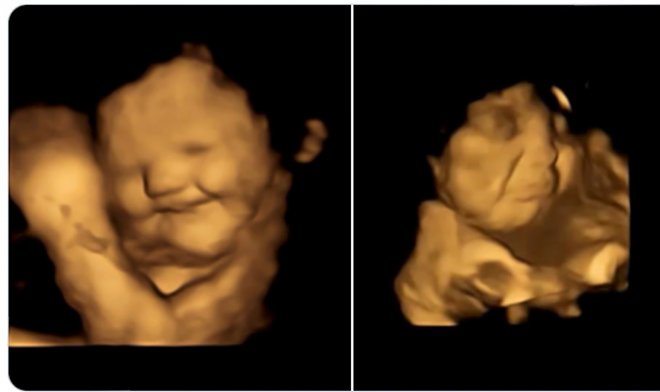

O estudo usou tecnologia avançada de varredura de ultrassom 4D, que permite a criação de imagens muito detalhadas do feto. O experimento envolveu cerca de cem mulheres no último trimestre de gravidez. O exame de ultra-som durou 25 minutos para rastrear os detalhes máximos do comportamento fetal e eliminar reações errôneas.

As mulheres receberam pílulas com pó de couve e cenoura. O primeiro tem um sabor amargo, o segundo é percebido como doce, embora não contenha açúcar. Como resultado, o scanner registrou uma reação distinta do feto - seus rostos enrugaram ou sorriram em resposta ao sabor amargo ou doce, respectivamente. Os dados foram testados em um grupo de controle que não recebeu nenhum sabor especial.